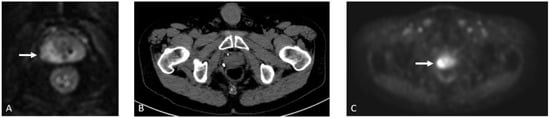

Detection of Loco-Regional Disease and Distant Metastases